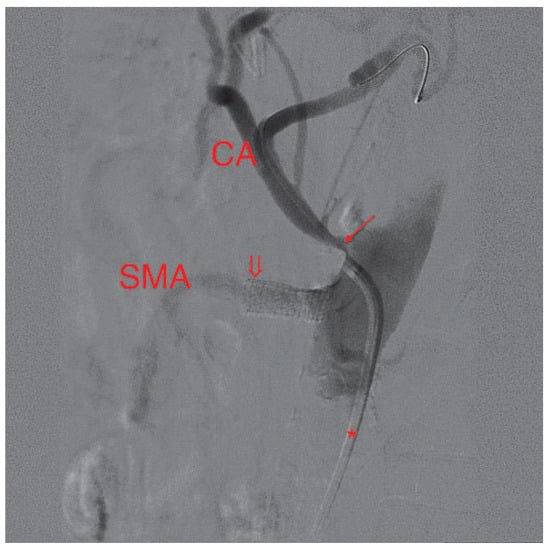

The coronary angiogram showed open coronary bypasses with no relevant progression of coronary atherosclerosis. Due to the clinical picture, suggesting mesenteric ischemia, selective angiography of the major splanchnic arteries was performed. It showed significant stenosis of the proximal superior mesenteric (SMA) and of the proximal celiac arteries (CA). The inferior mesenteric artery (IMA) and both renal arteries were normal.

In a first step, the SMA was treated by balloon angioplasty and a bare metal stent (hippocampus 7.0/20 mm) was implanted. After 2 weeks, the patient was readmitted with improved but not completely resolved abdominal symptoms. The remaining stenosis of the CA was revascularised, using another bare metal stent (hippocampus 6.0/20 mm). During a clinical follow-up of six months, the patient was asymptomatic.

Figure 1. In this lateral view, the catheter (*) in the abdominal aorta can be seen left of the spine. Its tip lies selectively in the superior mesenteric artery (SMA). The severely narrowed neck of the SMA can be clearly seen (arrow).